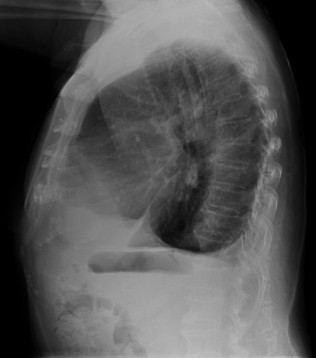

CASO: Febrícula y tos de 4 días de evolución.

Hallazgos:

- En la placa PA se observa una asimetría en los hilios pulmonares, el hilio izquierdo tiene una densidad aumentada.

- Tras examinar la placa lateral se observa un aumento de densidad en la columna que puede ser compatible con una condensación, es el signo de la desnificación vertebral.

SIGNO DE LA DENSIFICACIÓN VERTEBRAL: En la radiografía lateral normal, la densidad de la columna torácica tiende a disminuir desde la parte superior hasta el diafragma; la alteración de ese patrón por la presencia de una densidad superpuesta a la columna, indica la existencia de una consolidación pulmonar. Este signo adquiere especial valor cuando en la proyección posteroanterior la consolidación está oculta en el espacio retrocardíaco o en la base pulmonar.